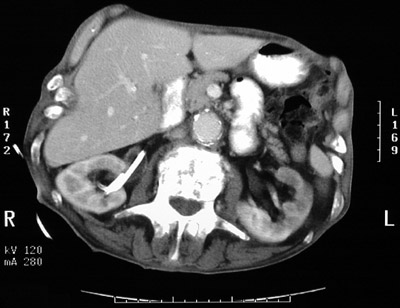

| This abdominal CT scan with contrast demonstrates right hydronephrosis as a consequence of ureteral obstruction. The pelvis and proximal ureter are dilated. The view below was obtained after placement of a stent from bladder to ureter to provide drainage. The stent is bright. |